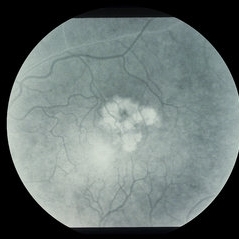

ARMD Laser Rx

Condition/keywords: wet age-related macular degeneration (wet AMD)